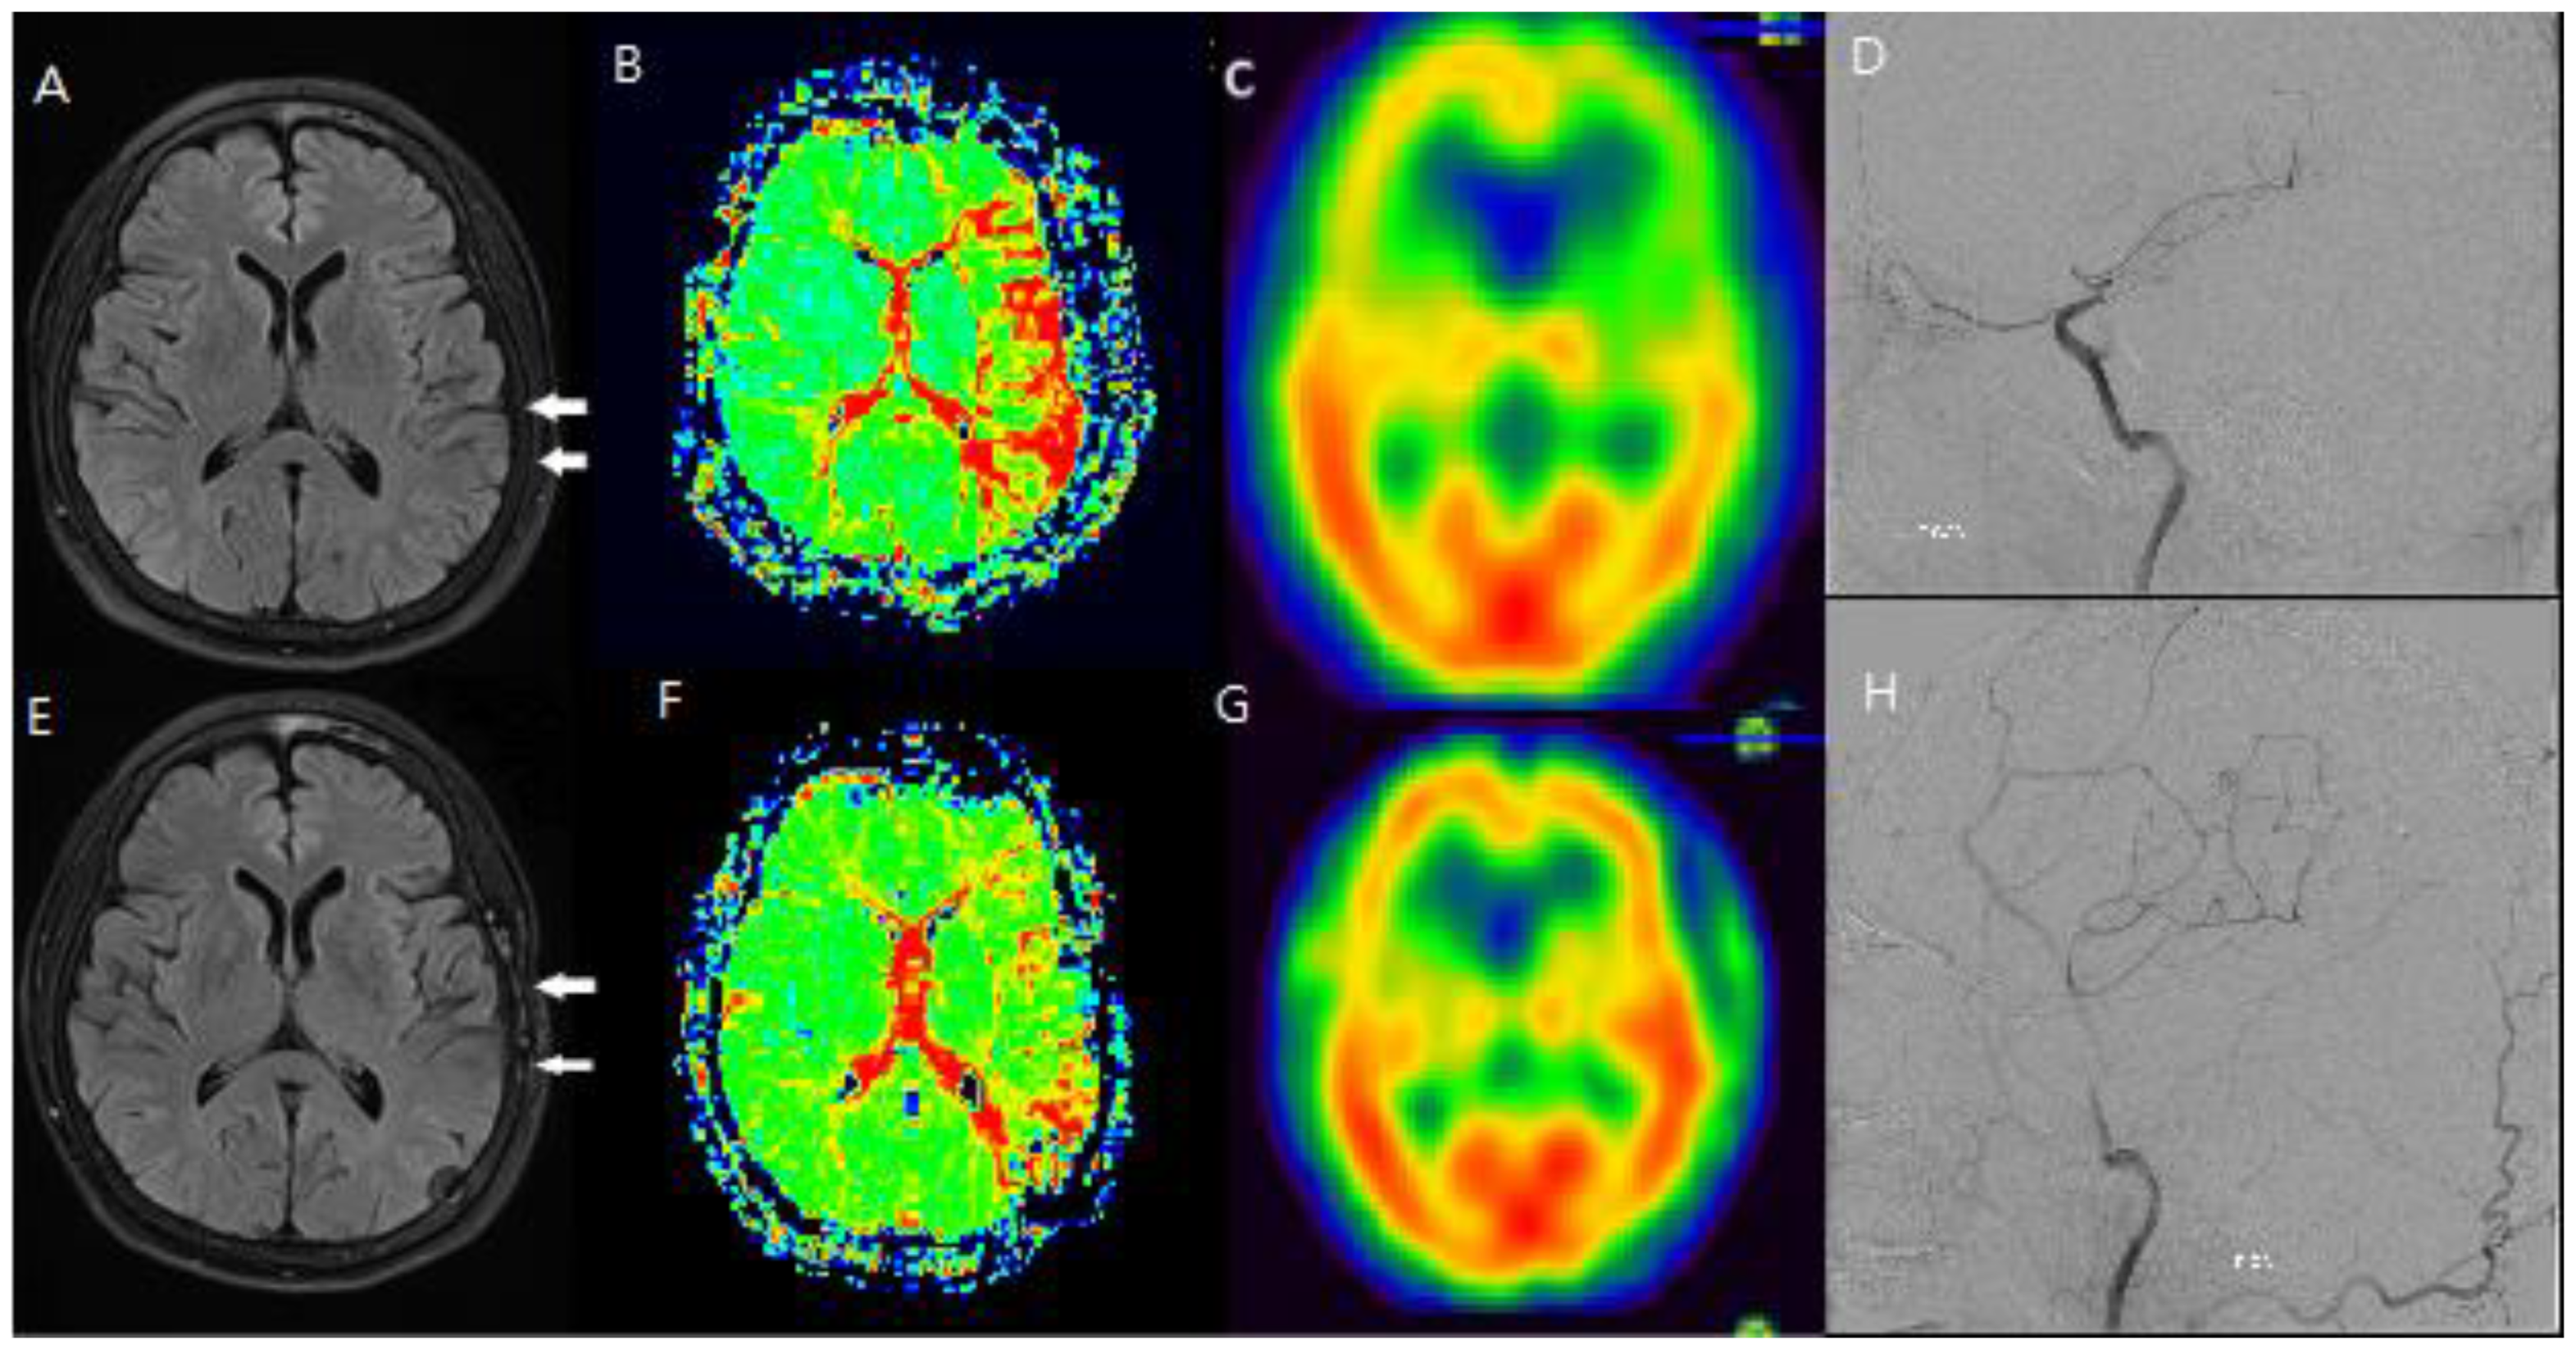

Figure 1. F/64 moyamoya disease patients. Preoperative (A, B, C, D) and postoperative (E, F, G, H) MR FLAIR, perfusion MR and SPECT shows improved HV and CVR after STA-MCA bypass (White arrow: Hyperintense vessels and decreased CVR on same region).

Forty-nine patients were diagnosed with moyamoya disease and symptomatic steno-occlusive disease on angiography, and they underwent STA-MCA anastomosis. As a result, the sum of CVR in all patients on post-contrast SPECT images was 3035 preoperatively and 3480 postoperatively (p < 0.05), and the surgery was successful in all patients. Among these patients, MR FLAIR and SPECT images were checked after the anastomosis (Figure 1).

To evaluate the usefulness of the ivy sign for follow-up, changes in the ivy sign on MR FLAIR images were compared with changes in CVR on SPECT images before and after STA-MCA anastomosis.

Additionally, changes in the ivy sign on MR FLAIR images were compared with MR perfusion images. The degree of change in mean transit time (MTT) was greater in areas with positive or minimal HV compared to areas with negative HV. After STA-MCA bypass surgery, regions where HV decreased or disappeared showed improved hemodynamics, as reflected in both SPECTand MR perfusion imaging (Figure 2).